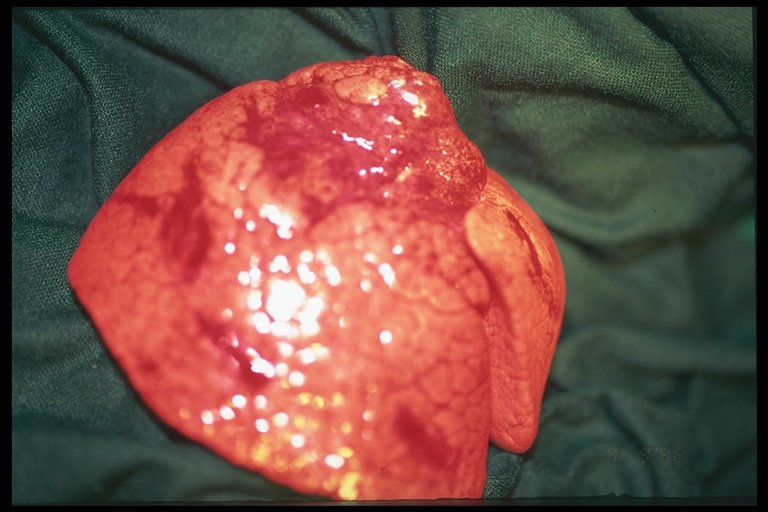

Operative finding in a case of cystic adenomatoid right lung